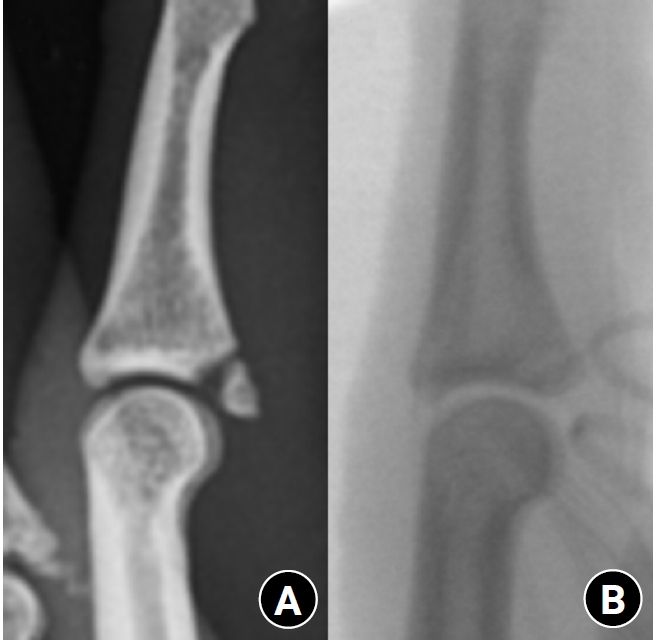

Fig. 2.

Radiographs of a middle phalanx avulsion fracture. (A) Initial fracture. (B) Reduction after open reduction.

The surgical procedure was similar to that described by Kang et al. [3] and Thirumalai et al. [4]. All procedures were performed under general or regional anesthesia. A volar Bruner or zigzag incision was made to expose the PIP joint. The flexor tendon was retracted, and the volar plate was identified between the flexor tendons and the collateral ligament. The fracture fragment was visualized and meticulous dissection was performed to preserve soft-tissue attachments and vascularity. The hook plate was fabricated from a 1.5-mm modular hand system titanium plate (Synthes). A two- or three-hole plate was modified into a hook plate depending on the requirement. The cut ends of the plate were bent into hooks (Fig. 1). Anatomical reduction of the fracture fragment was successfully achieved using the hook plates (Fig. 2). Subsequently, the hooks were passed through these slips around the edge of the joint at the distal edge of the fracture fragment. They grabbed onto the lip of the articular surface in an area that does not interfere with joint function. Then, the hooks were used to control and reduce the fracture fragment. A 0.9-mm K-wire could be used to help reduce and hold the fracture fragment temporarily while applying the plate. The plate crossed the fracture line and was fixed with a single screw distal to the fracture (Fig. 3). Fixation stability was confirmed by passively moving the joint through a full passive ROM under C-arm fluoroscopy. After surgery, the finger was immobilized in a functional position using a dorsal blocking splint for one week. Gradual active and passive ROM exercises were initiated thereafter under protective splinting, and unrestricted use was permitted after radiographic confirmation of bone union.